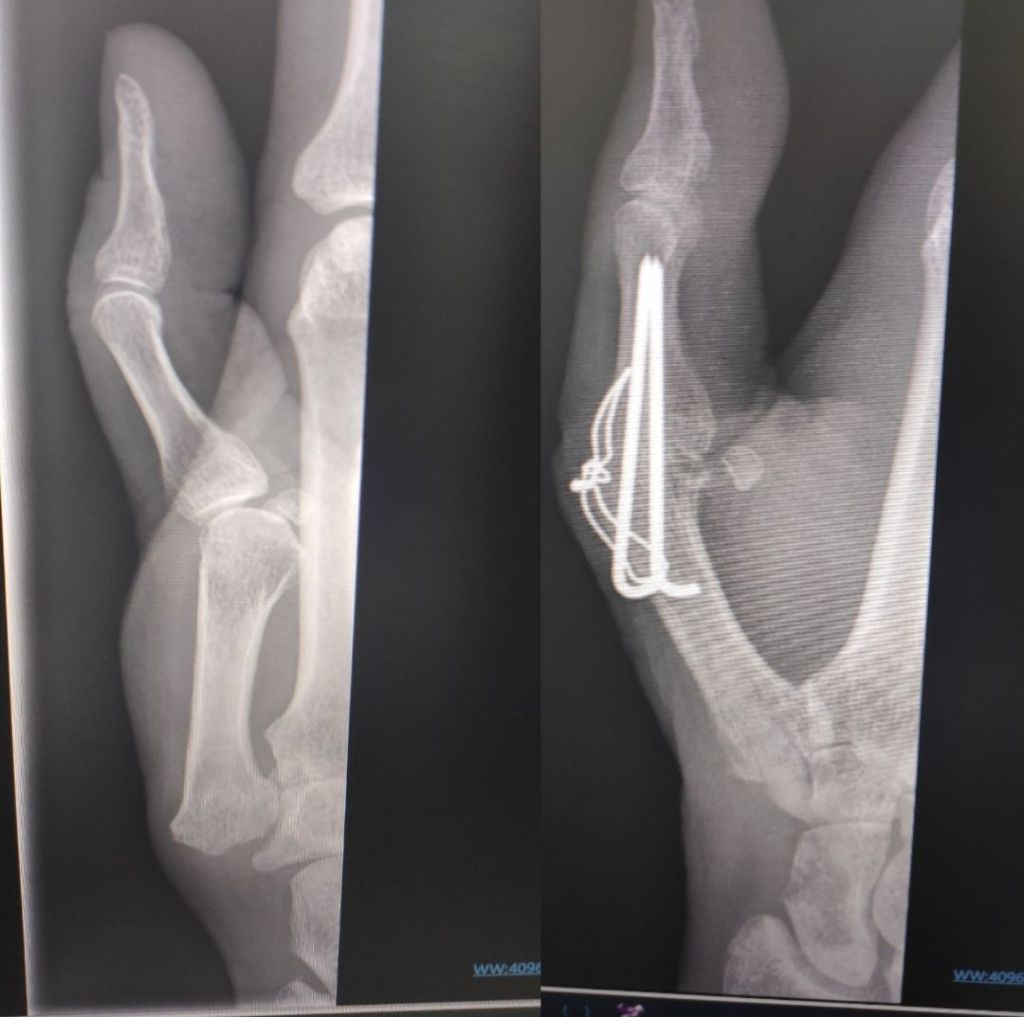

For my hand i rung up to enquire about having the tension band wire removed, as i constantly knock it. I was meant to have a follow up xray way way back in Sept, but they forgot, I got super busy over October and November, and boom it’s 2025 already. So I promised myself I would do better and I’ve booked in for 24th February.

Just the thin wire i want removing.

Where the wire is twisted together is where I catch it.

The skin over the wire is quite thin, and I fear it will poke out. And the scar tissue is building up, making the nobble bigger and bigger.